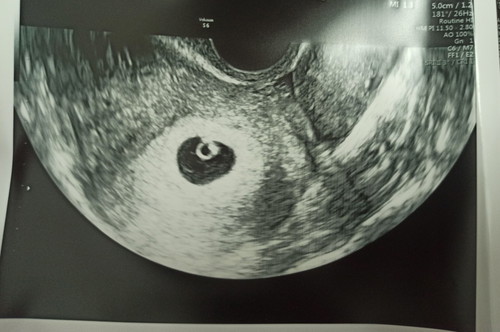

ตั้งครรภ์ไตรมาสแรก บ้านนี้อยากได้ลูกสาวทั้งบ้านเลยค่ะ แต่ลองทดสอบด้วยบททดสอบต่าง ๆ รวมทั้งปฏิทินจีน ทายว่าได้ลูกชายหมดเลย แอบใจแป้วนิด ๆ เพราะอยากได้ลูกสาวมาก แม่ชอบกินของหวาน น้ำหวาน ผลไม้หวาน ๆ ชอบกินเมนูเส้น คลั่งรักสามีมาก ไม่แพ้ ไม่อ้วก หน้าไม่มีสิว มีบ้าง 1-2 เม็ด เล็ก ๆ (ปกติเป็นคนไม่เป็นสิวอยู่แล้ว) กินข้าวได้แค่ครึ่งทัพพี ก็กันไปหาของหวานแล้ว อาการนี้มีแต่คนบอกว่าได้ลูกสาวแน่นอน แต่ในบททดสอบต่าง ๆ บอกได้ลูกชายหมดเลย กว่าจะได้ซาวด์รู้เพศลูกต้องรอถึง 18-20 สัปดาห์ เราอยากรู้ว่ามีใครเป็นแบบนี้ แล้วได้ลูกเพศไหนบ้างคะ มาแชร์กันค่ะ #เพศลูก

ตั้งครรภ์อยู่